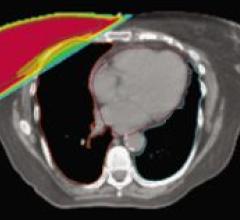

GE Healthcare is extending its Discovery product line with the introduction of the new Discovery PET/CT 600. This system ...